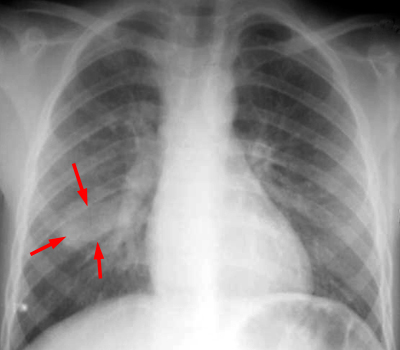

| Example of a "round pneumonia." PA and LAT CXR shows a round opacity in the superior segment of the right lower lobe which has the appearance of a mass. |